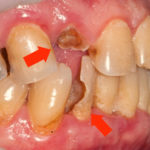

- остатки зуба поражены глубоким кариесом и их восстановление нецелесообразно или невозможно;

- пеньки зубов окружены воспаленными или инфицированными тканями;

- на деснах в области разрушенного зуба определяются признаки гиперплазии (патологического разрастания тканей);

- Изменения в деснах. Отсутствие нагрузки на разрушенный зуб или хроническая травма, причиняемая деснам при жевании, может вызвать пародонтоз или гиперплазию десен. В первом случае десны заметно уменьшаются в объеме, становятся бледными и атоничными. При гиперплазии наблюдается противоположная картина — мягкие ткани чрезмерно разрастаются и могут даже покрывать остаток зуба.